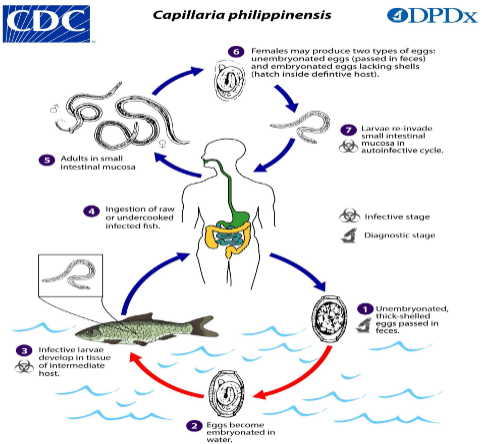

life cycle of capillaria philippinensis

unembryonated, thick shelled eggs are passed in feces

eggs embryonated in water

infective larvae develop in tissue of intermediate host (fish)

humans ingest raw/undercooked fish

larvae mature into adults in small intestinal mucosa

females will produced unembryonated eggs (passed in feces) & embryonated eggs that hatch in definitive host

larvae re-invade small intestinal mucosa in autoinfection

answer the following about c philippinensis:

What form is shed/acquired from the human?

If, an egg, is it embryonated or not?

If it is a larvae, what kind of larvae?

What hatches from the egg?

unembryonated eggs shed from the human

infective larvae hatch from eggs in intermediate host tissue

answer the following about c philippinensis:

intermediate host? reservoir host?

What is the infective stage that gets back into the human?

How does the infective stage get back into the human?

General info about what happens once it gets back into the human.

Where do adults live?

intermediate: fish ; reservoir: humans/fish

infective stage: larvae inside intermediate host

humans ingest raw/undercooked fish

larvae develops into adults and contribute to auto-infective cycle (need 2 worms to fertilize eggs)

adults: small intestinal mucosa